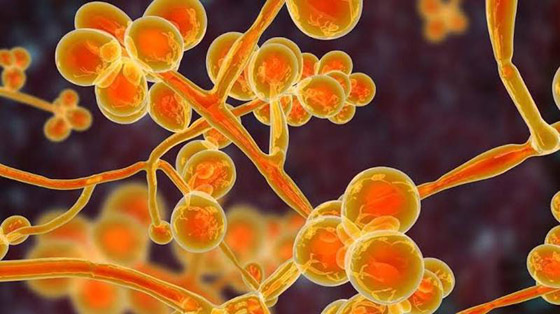

ما هو الفطر الأصفر؟

يغزو الفطر الأصفر الأعضاء الداخلية للجسم ويؤثر على أدائها الوظيفي بالكامل، ولا ينطلق الفطر الأصفر من الرئتين بالضرورة، ويتشكل بسبب وجود نوع من الفطريات التي تتكاثر لتهاجم الجسم بأكمله. قد تترافق الإصابة بالفطر الأصفر بالطفح الجلدي وحرقة الجلد والإرهاق، ومن الممكن أن يصبح شديداً وخطيراً للغاية إذا لم تتم معالجته بسرعة. ويعتمد مدى انتشار الفطر الأصفر في جسد المريض على حالة المريض الصحية وقوة مناعته، ولكيلا يصبح الأمر خطيراً ينبغي التركيز دائماً على الوقاية من هذا المرض.

كيف يختلف الفطر الأصفر عن الفطر الأبيض؟

يمكن أن تكون العدوى بالفطر الأبيض أكثر خطورة من العدوى بالفطريات السوداء. إذ لا يؤثر الفطر الأبيض فقط على الرئتين ولكن أيضاً على أجزاء أخرى من الجسم مثل الأظافر والجلد والكلى والدماغ وغيرها. يمكن أن تحدث العدوى بسبب ضعف المناعة أو إذا كان الأشخاص على اتصال بأشياء تحتوي على فطريات العفن مثل الماء الملوث.

ويقول الدكتور أرونيش كومار رئيس طب الجهاز التنفسي وأمراض الرئة بمستشفى باراس: "يُظهر مرضى الفطر الأبيض أعراضاً شبيهة بأعراض فيروس كورونا لكن نتيجة الاختبار تظهر سلبية؛ ويمكن تشخيص العدوى بالفطر الأبيض من خلال التصوير المقطعي أو الأشعة السينية". وبالتأكيد فإن المرضى الذين يعانون من نقص المناعة تزداد مخاطر إصابتهم بالعدوى الفطرية بشكل أكبر، وهذا ينطبق على الفطر الأبيض والأسود والأصفر.